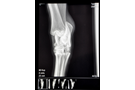

Vi gör alla typer av besiktningsröntgen (exportröntgen, hingströntgen, travarröntgen, hovbroskröntgen och unghäströntgen). Dessutom kan vi röntga halsar, ryggar, tänder, akuta frakturer m.m.